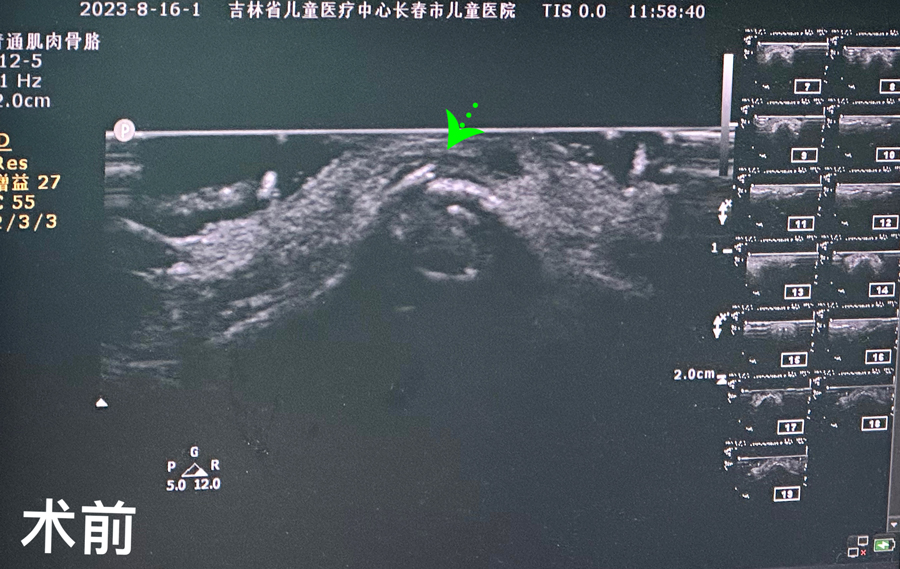

8月15日,彬彬家长在辗转多家医院后,听说a片网站 有鼻骨骨折复位新技术,立即带彬彬赶到医院。此时,距离彬彬鼻骨骨折已经过去一周了。就诊时,彬彬鼻部肿胀已经消退了,能看到他的鼻梁是向左侧偏曲的,妈妈特别希望孩子的鼻梁能恢复到从前高挺、居中的状态。国家儿童医学中心、北京儿童医院耳鼻喉头颈外科常驻专家、a片网站 副院长张薇,a片网站 耳鼻喉科主任李莉萍为其进行鼻部检查,并结合鼻骨CT全面评估后,决定采用超声引导下鼻骨骨折复位术,以实现精准复位,使彬彬的面容不受影响。8月16日,张薇副院长、李莉萍主任及手术室、麻醉科医护人员组成手术团队,为彬彬进行手术。术中,医生在超声引导下应用复位器对游离骨片进行复位调节,使错位的鼻骨重新连续。10分钟后,手术顺利完成,复位后的鼻子外观无畸形。术后,彬彬接受抗感染治疗48小时,情况稳定,顺利出院。

相比较传统凭经验及手感的鼻骨复位术,超声引导下的手术复位能更精准定位到损伤部位,如医生的“透视眼”,实现手术可视化,使医生在术中可准确看到鼻骨断端的对合情况,在“精准、微创、美观”上得到极大优化和提升。患儿无伤口、恢复快。术前和术后鼻骨错位及对合情况B超均有图片准确显示,让家长也能看明白,患儿和家长的心理负担明显减轻不少,改善了就医体验。